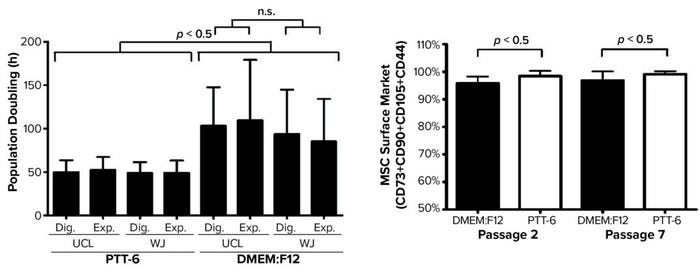

Next, to determine the proliferation rates for isolated MSCs under the investigated conditions, we plotted mean PDT graphs and compared the results (Figure 4, left). Cells cultured in PTT-6 medium showed significantly shorter PDTs (50.1 ± 9.7 hours) than those in DMEM:F12 (98.4 ± 37.5 hours). Note that the PDT of PTT-6–cultured cells remains stable, with much less fluctuation than for cells in DMEM:F12, making PTT-6 medium a better candidate for manufacturing process standardization. Cells cultured in that medium showed no significant difference in PDT regardless of tissue source or extraction method. This suggests that PDT depends more on the type of culture medium used than on either the extraction method or tissue source, with no significant differences observed (p > 0.05) when the same medium was used.

Figure 4: (LEFT) To compare mean ± SD population doubling time (PDT) across all experimented conditions, a total of six biological replicates were analyzed for each condition (Dig. = digest, Exp. = explant). (RIGHT) Purity profiles between passages 2 and 7 (P2, P7) reveal constant purity for all PTT-6–cultured MSCs after multiple passages; DMEM:F12–cultured MSCs displayed lower expression at P2, increasing by P7. Significant differences in cell-surface marker expression were seen for MSCs cultured in DMEM:F12 and PTT-6 at P2 and P7 (n.s. = not significant). Six total biological replicates were analyzed from each set of conditions.

Based on standards recommended by the International Society for Cell and Gene Therapy (ISCT), MSC purity is defined by positive expression of a group of specific surface markers —CD44, CD73, CD90, and CD105 — and a lack of expression for hematopoietic stem cell (HSC) surface markers CD34, CD45, CD11b, CD19, and HLA-DR. Decreasing expression levels of MSC-specific surface markers implies a cell purity reduction. So we compared the purity of MSCs cultured in different conditions across passages by examining the expression levels of MSC-specific markers (Figure 4, right). Tabulated flow-cytometry results revealed that PTT-6–cultured cells maintained persistent high purity across multiple passages (98.4 ± 1.9% at P2, 99.1 ± 1.1% at P7), whereas DMEM:F12–cultured cells expressed marginally lower levels of those markers at P2 (95.8 ± 2.5%) that increased by P7 (96.8 ± 3.3%).

When we compared tissue sources and extraction methods, we found no observable differences in MSC purity (data not shown), which indicates that it is medium dependent. No cultured cells expressed HSC surface markers. PTT-6–cultured cells demonstrated significantly higher surface-marker expression than did DMEM:F12–cultured cells (p < 0.05) at both P2 and P7 (Figure 4, right). On comparing the median fluorescence intensity (MFI) of individual MSC biomarkers from P2 and P7 (Figure 5), we found increased CD73 expression in DMEM:F12 cultured cells and an increase in the expression of CD90 in PTT-6–cultured cells.